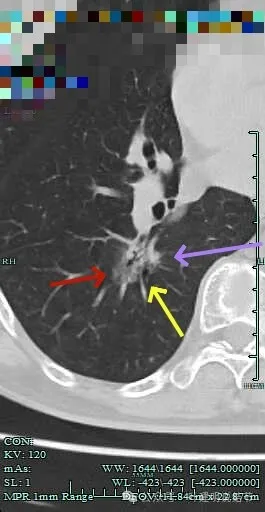

密度杂乱,毛刺明显,支气管僵硬。

杂乱密度,整体轮廓较清,边缘毛糙。

斜裂根部有增厚并与病灶连着。考虑是肿瘤已经侵及叶间裂。

病灶边缘毛刺明显。

肺磨玻璃结节我们常说瘤肺边界清楚加上随访持续存在,基本上是肺癌性质的。但像今天这种混合磨玻璃密度的病灶,你看它瘤肺边界却是不清楚的,只是整体轮廓相对较清。但它的瘤肺边界是布满细毛刺的,而且是短毛刺且锐利,在影像上就像刺入周围正常肺组织中。这种影像表现的我将它称为“浸润性生长的影像表现”,说明病灶是浸润性病灶,而非原位癌或良性。这样的病灶不宜过度随访,需要及时干预更为稳当。